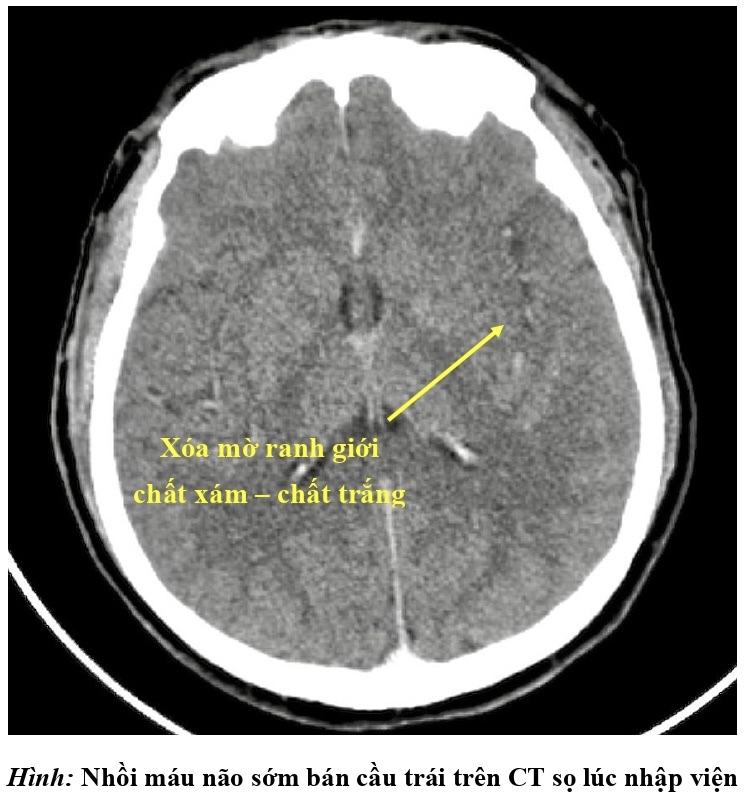

Ngay lập tức, bệnh viện kích hoạt quy trình báo động đột quỵ (code stroke). Khẩn trương thăm khám lâm sàng và cận lâm sàng, các bác sĩ chẩn đoán bệnh nhân bị đột quỵ nhồi máu não bán cầu trái giờ thứ 2 do tắc động mạch cảnh trong trái và động mạch não giữa trái bởi huyết khối.

Hình chụp CT của bệnh nhân S.

Toàn bộ bán cầu não bên trái bị ngừng cung cấp máu, đe dọa nghiêm trọng tính mạng bệnh nhân, các bác sĩ phải chạy đua với thời gian cứu chữa người bệnh.